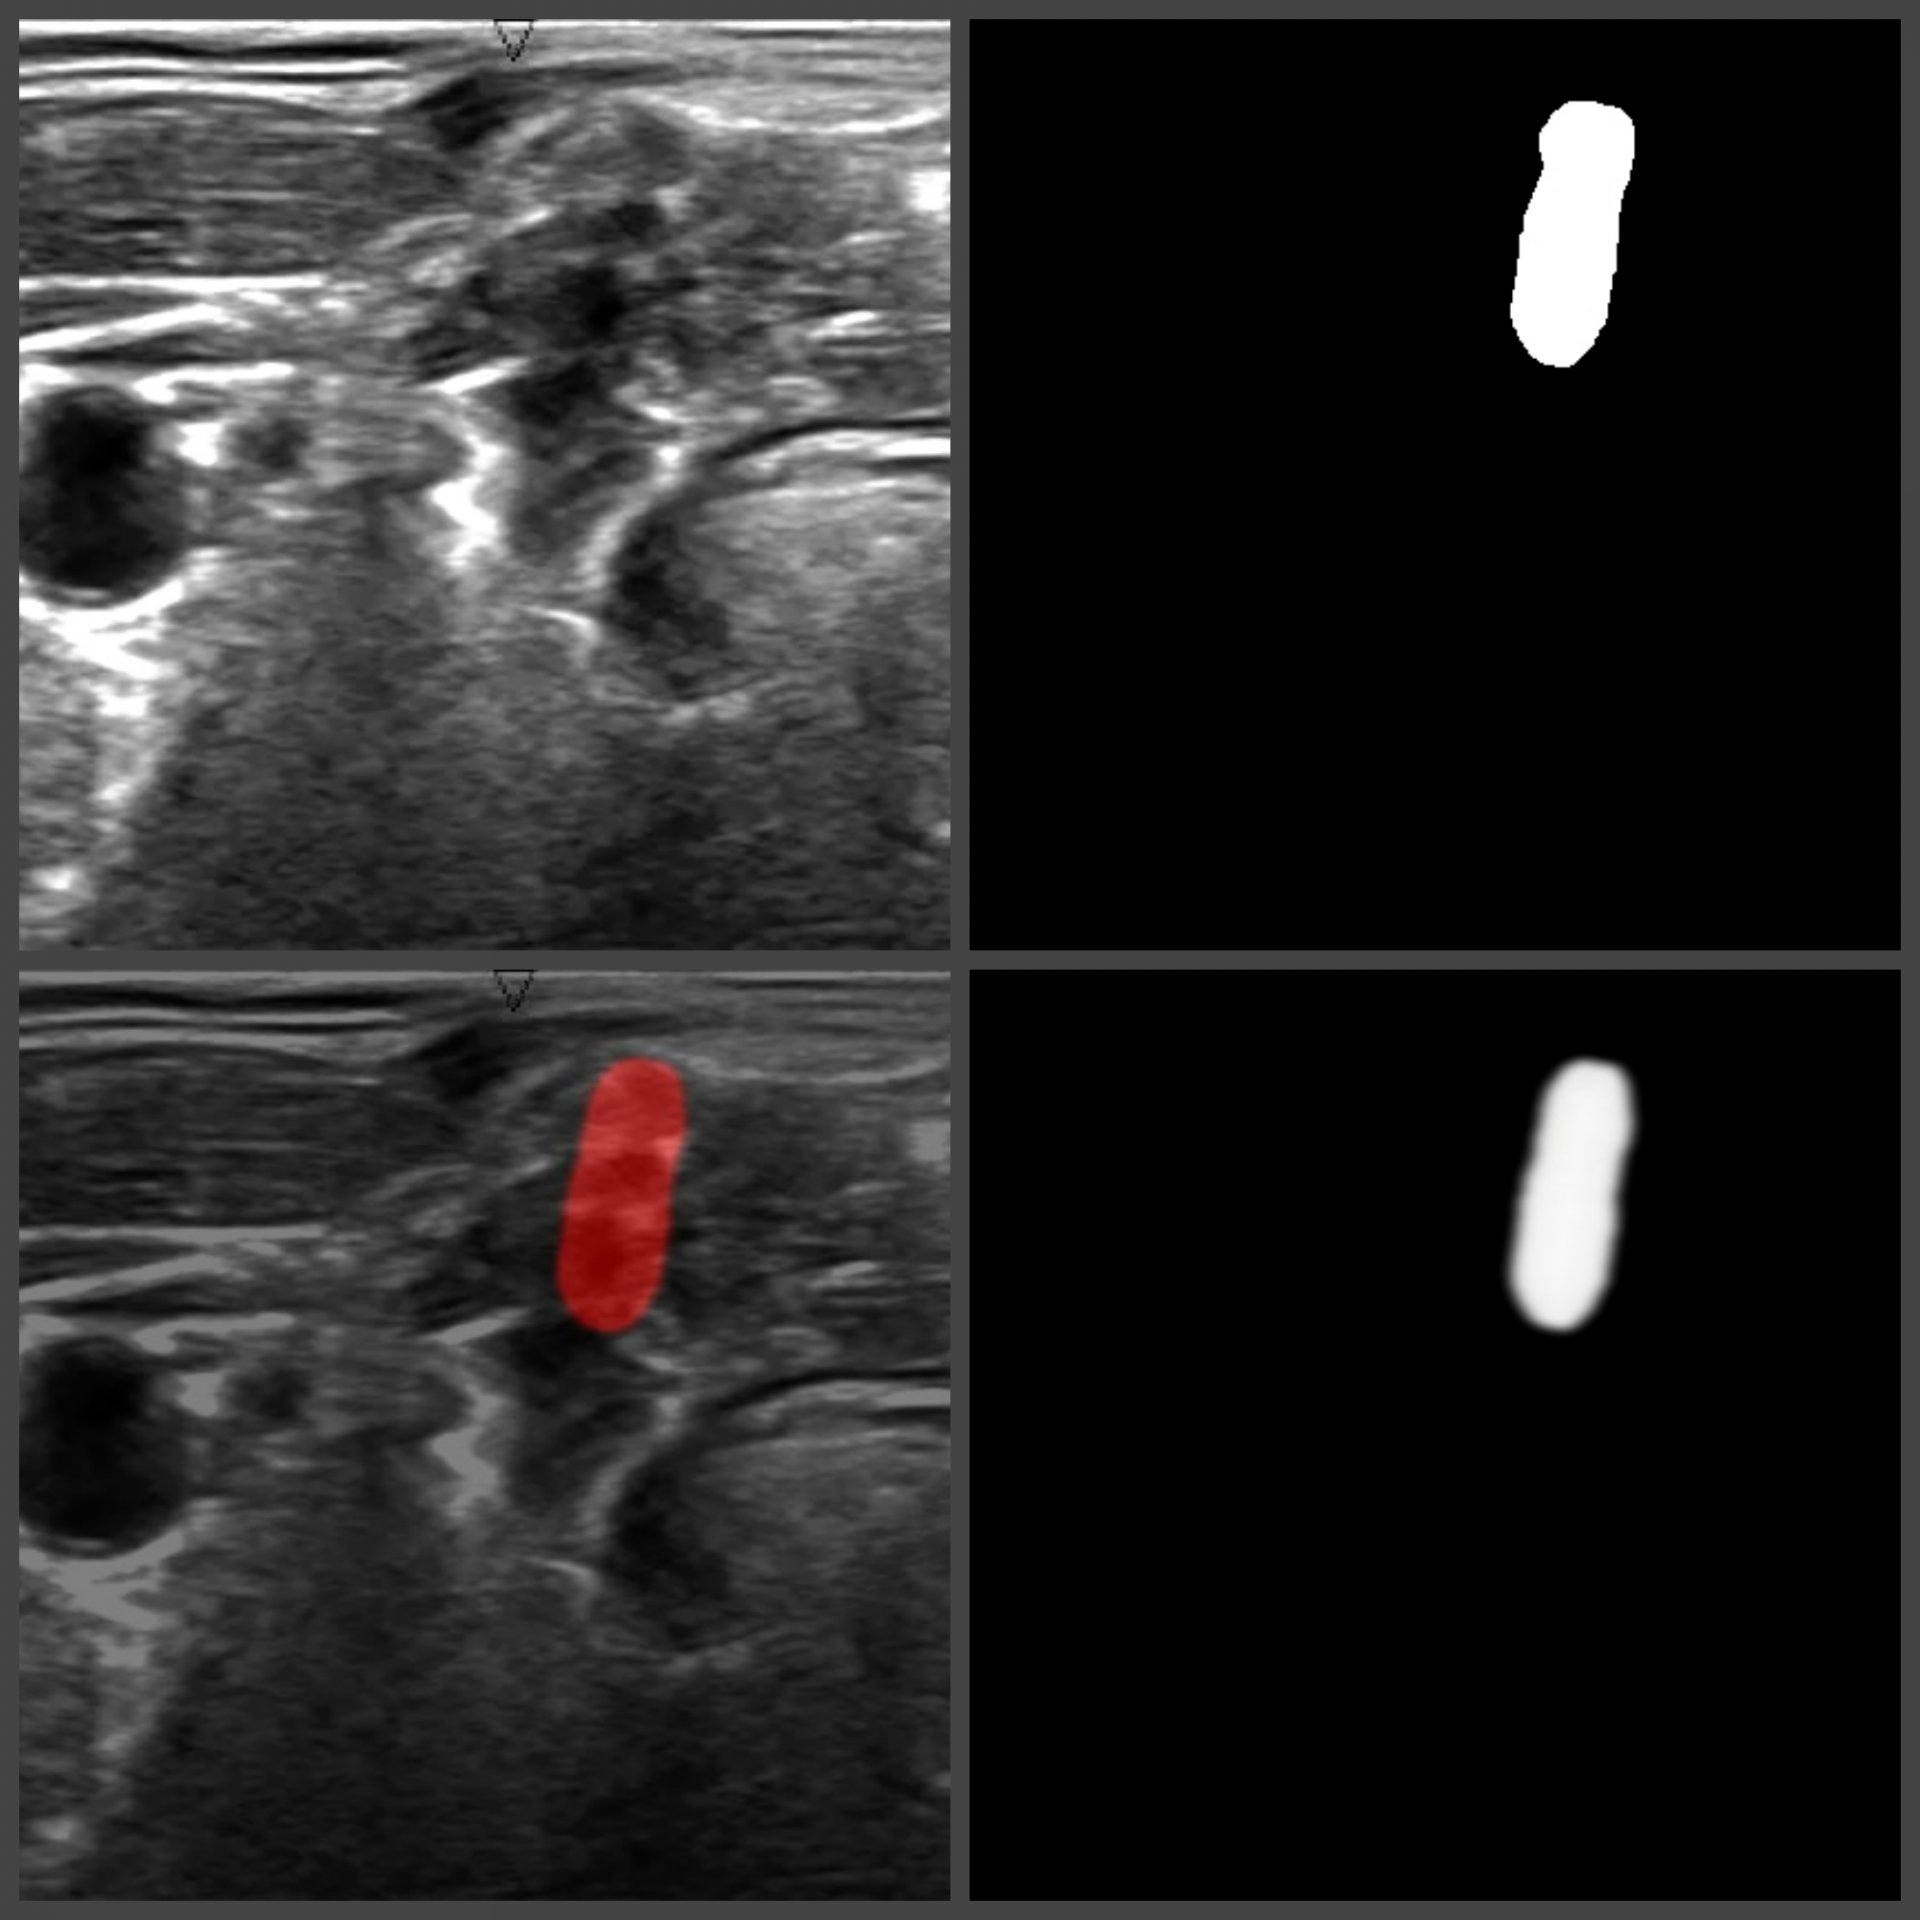

The project comes up with the solution which allows users to detect a brachial plexus on the ultrasound picture and the exact area in the patient’s body to implant the catheter. To achieve this, Computer Vision and machine learning technologies are applied.

To solve this problem, we chose UNet architecture. It is a special neural network architecture developed for biomedical images segmentation. The hyperparameters tuning has shown that the maximum accuracy in recognition is achieved through the combination of Dice + Binary Crossentropy as a loss function.

As a result, a script connected with the neural network was developed. The ultrasound image of the shoulder joint comes as an input. As an output, there is an image with the highlighted brachial plexus. Since it is a script, it can be used in any type of apps (web, desktop, mobile). The proper neural network training and setting has allowed getting ~70% accuracy in recognition.